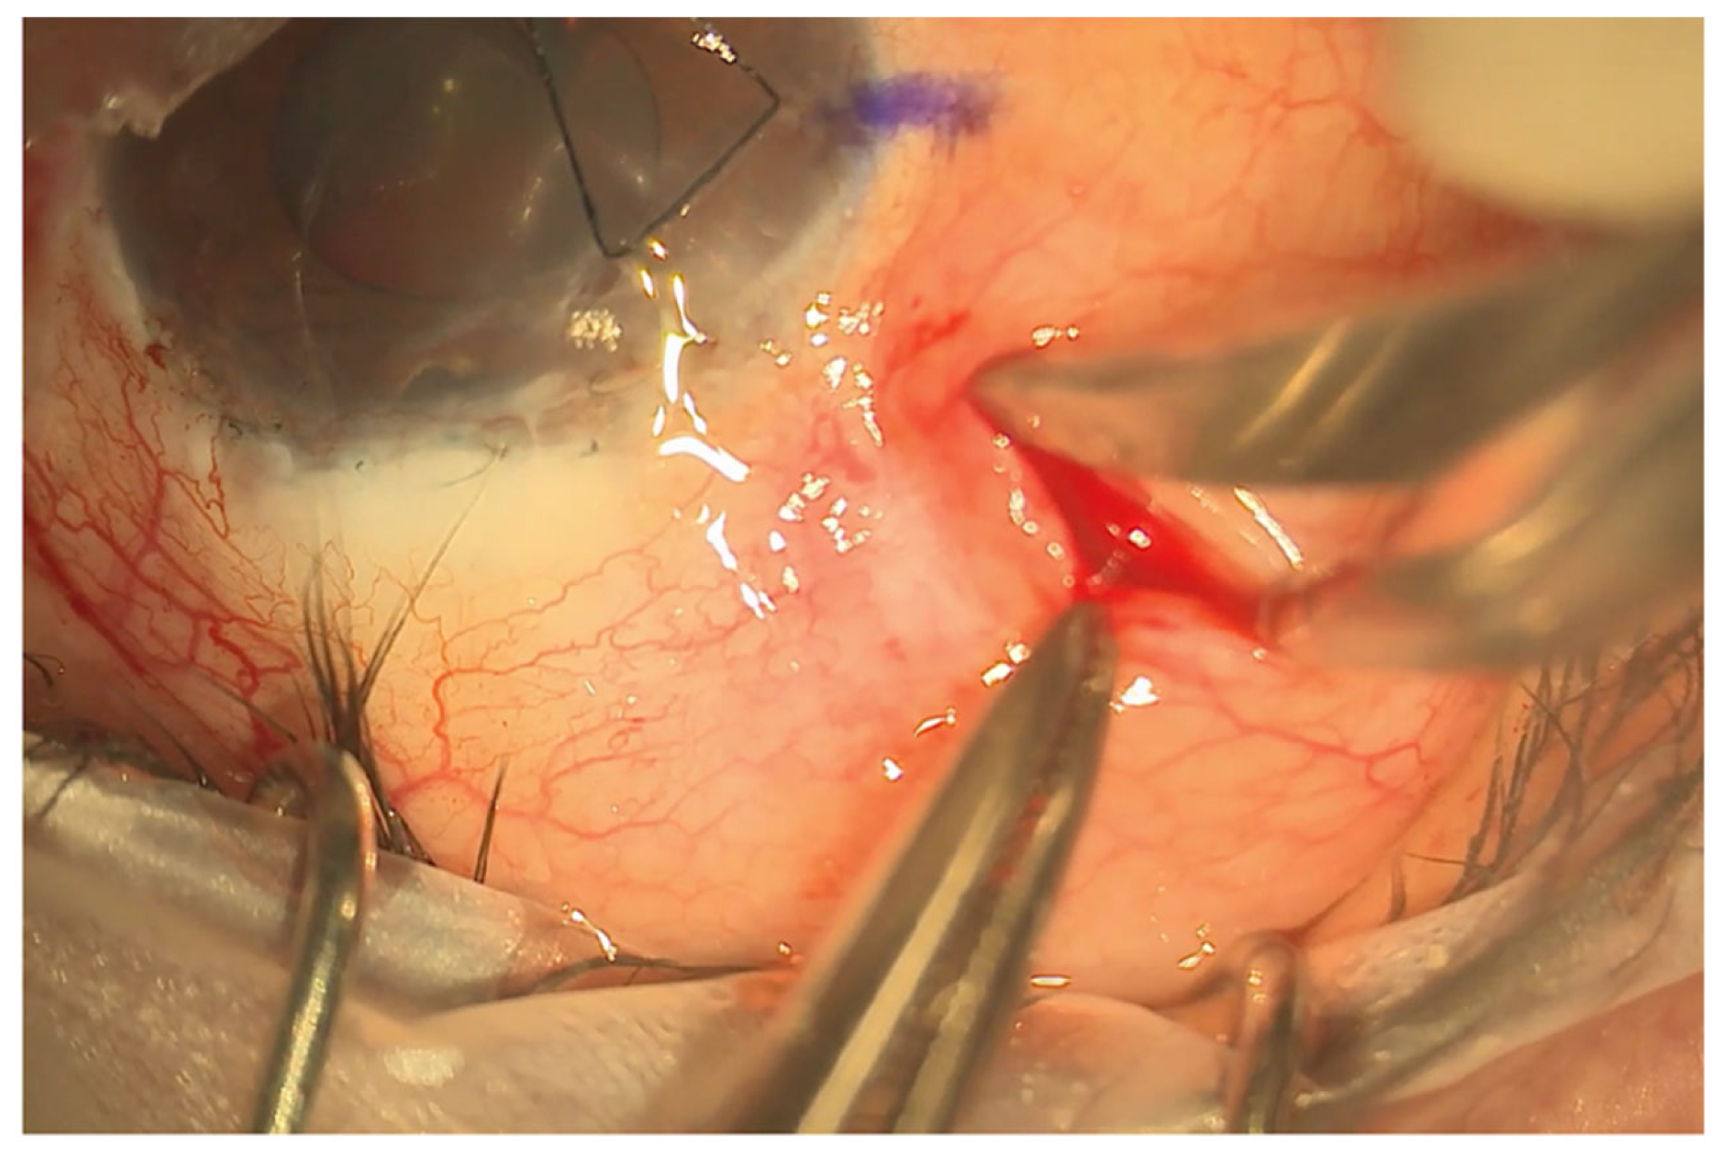

Figure 2.

Limbal sparing radial pocket. This is placed 5 mm behind the limbus and extended approximately 8–10 mm posteriorly.

The eyePlate-300 is ideally placed in the superotemporal quadrant. A 7/0 silk corneal traction suture is placed, and the eye is retracted inferonasally to expose the superotemporal quadrant. To create the conjunctival pocket, a subconjunctival injection of bupivacaine with adrenaline is injected behind the limbus mid-way between the superior and lateral rectus. This step helps to ensure adequate exposure of the conjunctiva and induces haemostasis. A vertical radial incision is then made 5 mm behind the corneal limbus with spring scissors extending posteriorly, approximately 8–10 mm in length. The conjunctiva is then dissected through this pocket to expose the bare sclera up to the lateral and superior recti. Haemostasis is further augmented with the use of cautery as required.

A 4/0 prolene suture is then fed into the tube to stent the eyePlate-300 tube. The eyePlate-300 can then be manipulated with Moorfields and Jayles forceps to be folded “Taco Style’ (Figure 1b) before being inserted on the sclera through the small conjunctival pocket (Figure 2). Care should be taken to unfold the plate under the tenons. Identification of the lateral and superior rectus muscles should take place to ensure the plate sits between the muscles, therefore minimising the risk of post-operative diplopia.